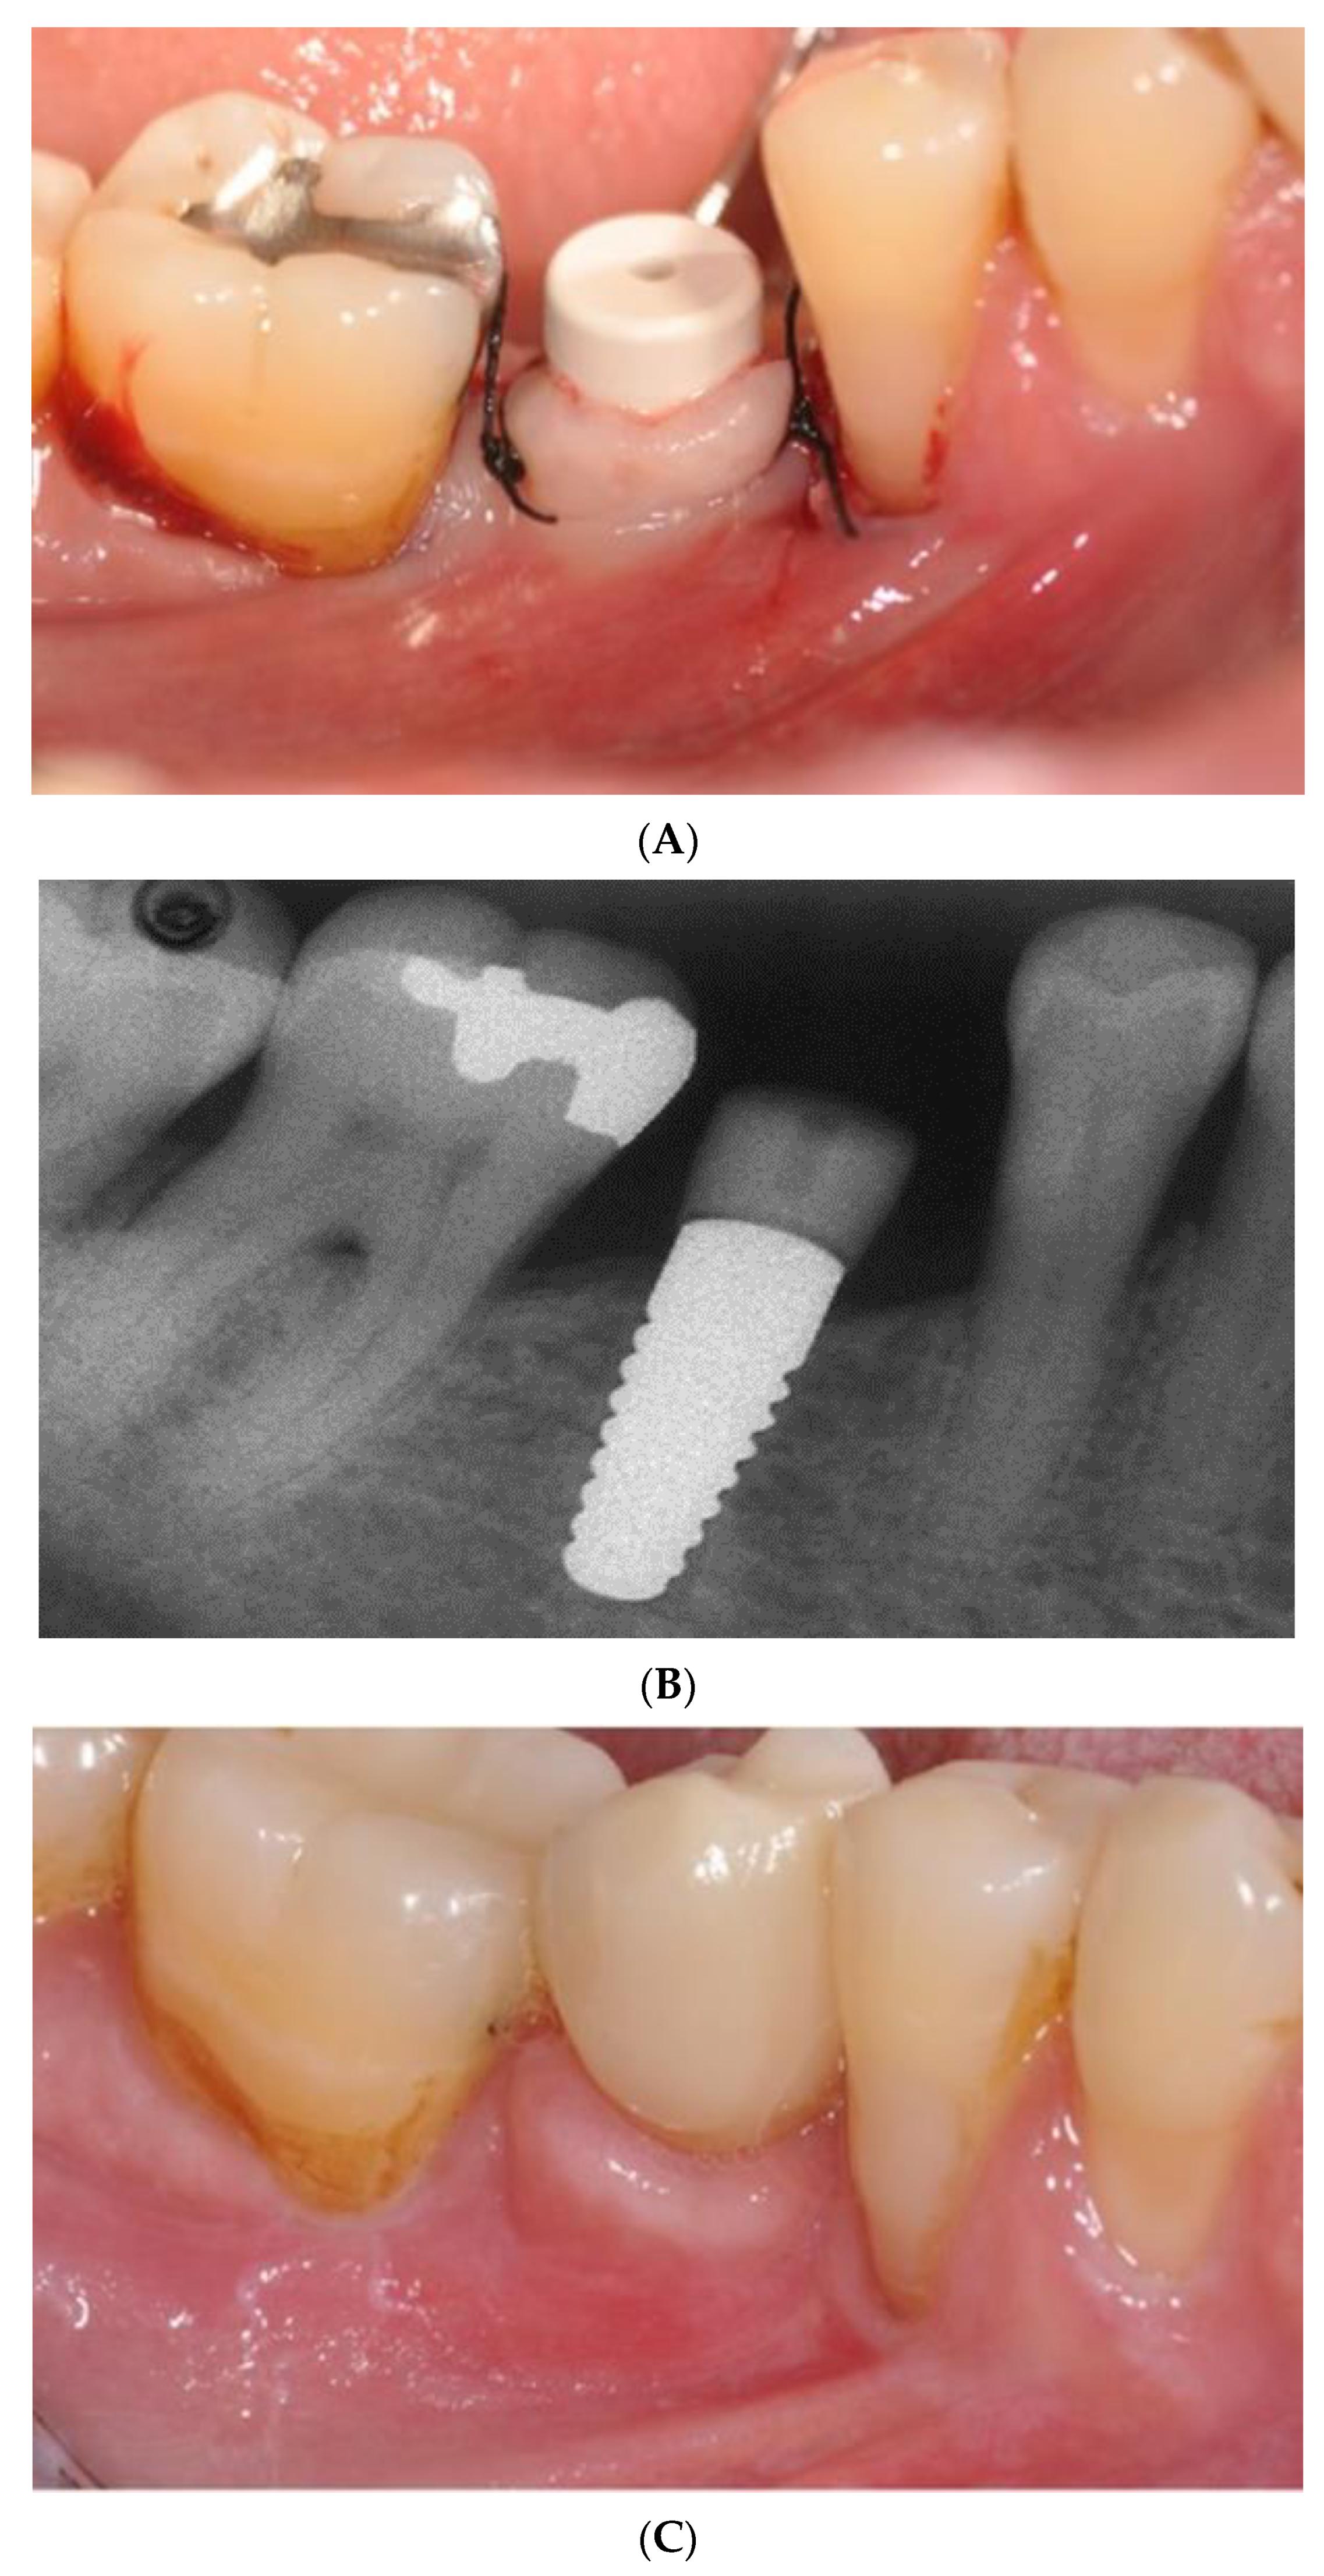

- Pirker, W.; Wiedemann, D.; Lidauer, A.; Kocher, A.A. Immediate, single stage, truly anatomic zirconia implant in lower molar replacement: A case report with 2.5 years follow-up. Int. J. Oral Maxillofac. Surg. 2011, 40, 212–216. [Google Scholar] [CrossRef]

- Pirker, W.; Kocher, A. Immediate, non-submerged, root-analogue zirconia implant in single tooth replacement. Int. J. Oral Maxillofac. Surg. 2008, 37, 293–295. [Google Scholar] [CrossRef]

- Pirker, W.; Kocher, A. Immediate, non-submerged, root-analogue zirconia implants placed into single-rooted extraction sockets: 2-year follow-up of a clinical study. Int. J. Oral Maxillofac. Surg. 2009, 38, 1127–1132. [Google Scholar] [CrossRef]

- Pessanha-Andrade, M.; Sordi, M.B.; Henriques, B.; Silva, F.S.; Teughels, W.; Souza, J.C.M. Custom-made root-analogue zirconia implants: A scoping review on mechanical and biological benefits. J. Biomed. Mater. Res. B Appl. Biomater. 2018, 106, 2888–2900. [Google Scholar] [CrossRef]

- Regish, K.M.; Sharma, D.; Prithviraj, D.R. An overview of immediate root analogue zirconia implants. J. Oral Implantol. 2013, 39, 225–233. [Google Scholar] [CrossRef] [PubMed]